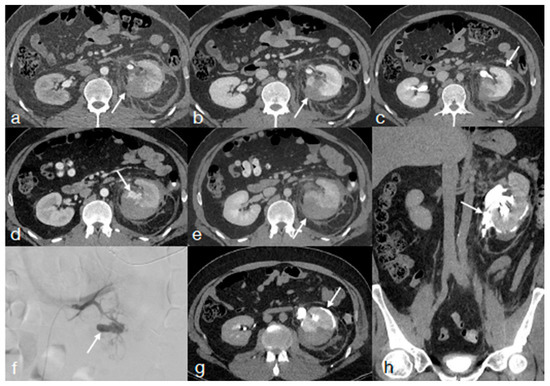

- Di Serafino, M.; Iacobellis, F.; Schillirò, M.L.; Ronza, R.; Verde, F.; Grimaldi, D.; Dell’Aversano Orabona, G.; Caruso, M.; Sabatino, V.; Rinaldo, C.; et al. The Technique and Advantages of Contrast-Enhanced Ultrasound in the Diagnosis and Follow-Up of Traumatic Abdomen Solid Organ Injuries. Diagnostics 2022, 12, 435. [Google Scholar] [CrossRef] [PubMed]